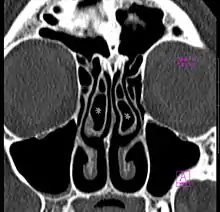

Concha bullosa

A concha bullosa is a pneumatized (air-filled) cavity within a nasal concha, also known as a turbinate.[1] Bullosa refers to the air-filled cavity within the turbinate.[1] It is a normal anatomic variant seen in up to half the population. Occasionally, a large concha bullosa may cause it to bulge sufficiently to obstruct the opening of an adjacent sinus, possibly leading to recurrent sinusitis.[1] In such a case the turbinate can be reduced in size by endoscopic nasal surgery (turbinectomy). The presence of a concha bullosa is often associated with deviation of the nasal septum toward the opposite side of the nasal cavity.[2] Although it is thought that sinusitis or sinus pathology has relation to concha bullosa, no strong statistical correlation has been demonstrated.[1]